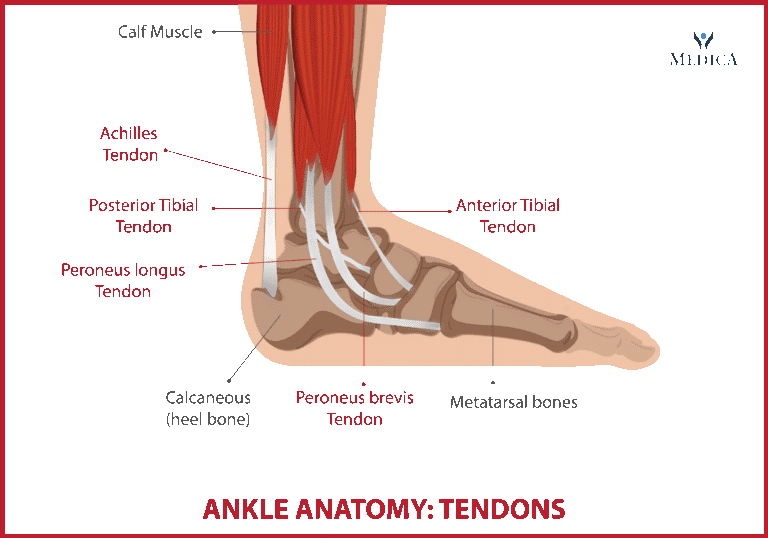

Dal punto di vista anatomico, la caviglia è stabilizzata da diversi complessi legamentosi: i legamenti laterali (in particolare il peroneo-astragalico anteriore, il più vulnerabile), il legamento mediale o deltoideo e i legamenti sindesmotici tibio-fibulari. Le distorsioni si verificano in seguito a movimenti eccessivi: le più comuni sono quelle in inversione, seguite da quelle in eversione e dalle sindesmotiche (“alta caviglia”), generalmente più gravi e con tempi di recupero più lunghi.

Le tendinopatie della caviglia sono frequenti negli atleti, con una prevalenza tra il 6% e il 18%, a seconda dello sport e delle caratteristiche fisiche. Sport come calcio, basket, atletica e corsa, caratterizzati da elevati carichi di lavoro e stress biomeccanici, aumentano il rischio di lesioni acute e croniche. I tendini della caviglia devono contrastare la forza peso e resistere a sollecitazioni importanti, risultando suscettibili di infiammazione, lesioni parziali o complete.

I tendini interessati in ordine di frequenza sono: tendine Achilleo, tendine Tibiale Posteriore, i Tendini Peronieri e il tendine Tibiale Anteriore.Il Tendine d’Achille è fondamentale nella spinta propulsiva del passo. La sua rottura, tipica di sport ad alto impatto, avviene per una contrazione eccentrica improvvisa del tricipite surale ed è favorita dalla presenza di degenerazione del tendine. Sensazione di schiocco, dolore e impotenza funzionale sono sintomi caratteristici. La diagnosi è clinica, confermata dall’ecografia o dalla risonanza magnetica. Il trattamento negli atleti è chirurgico per garantire una ripresa rapida e una corretta guarigione. Altro capitolo riguarda le tendinopatie achillee, comuni negli sport di corsa, hanno un’incidenza stimata tra il 7% e il 9% nell’atleta professionista.Sono divise in inserzionali (a livello calcaneare) o non inserzionali (sul corpo del tendine). Il trattamento conservativo prevede riposo, terapia fisica con esercizi eccentrici e utilizzo di plantari ortopedici. In caso di mancata risposta dopo 3-6 mesi, si può considerare l’intervento chirurgico. Seconde in ordine di frequenza le tendinopatie del tibiale posteriore interessano maggiormente atleti con piedi piatti o in chi pratica movimenti di pronazione eccessiva, come i ballerini poichè tale struttura stabilizza l’arco plantare e contribuisce alla spinta propulsiva. Il dolore segue il decorso del tendine, associandosi a gonfiore e limitazione funzionale. Il trattamento conservativo include l’uso di ortesi plantari, e chinesiterapia specifica. Nei casi refrattari, la chirurgia può prevedere la riparazione tendinea o la realizzazione di osteotomie correttive. I Tendini Peronieri, eversori del piede, sono spesso colpiti in atleti che praticano sport su superfici irregolari, come trail running e calcio. Il dolore può associarsi a schiocchi avvertiti in flessione plantare in caso di sublussazione dei tendini stessi. La tendinopatia risponde bene al trattamento conservativo,nei casi di lussazione dei tendini può rendersi necessario l’intervento chirurgico. Ultima per frequenza ma degne di menzione la tendinopatia del Tibiale Anteriore, che risulta maggiormente sollecitato in atleti che eseguono movimenti ripetuti di dorsiflessione, come i corridori in salita. Nelle fasi acute si procede in genere a trattamento conservativo con riposo, ghiaccio, fisioterapia. La chirurgia è riservata a casi con lesioni tendinee significative o risultati non soddisfacenti dopo 4/6 mesi di trattamento conservativo.